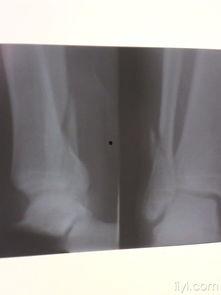

三、脚踝脱臼的图片

为了让你更直观地了解脚踝脱臼,以下是一些真实的图片:

从这些图片中,你可以看到脚踝脱臼后的严重程度,以及肿胀、畸形等症状。